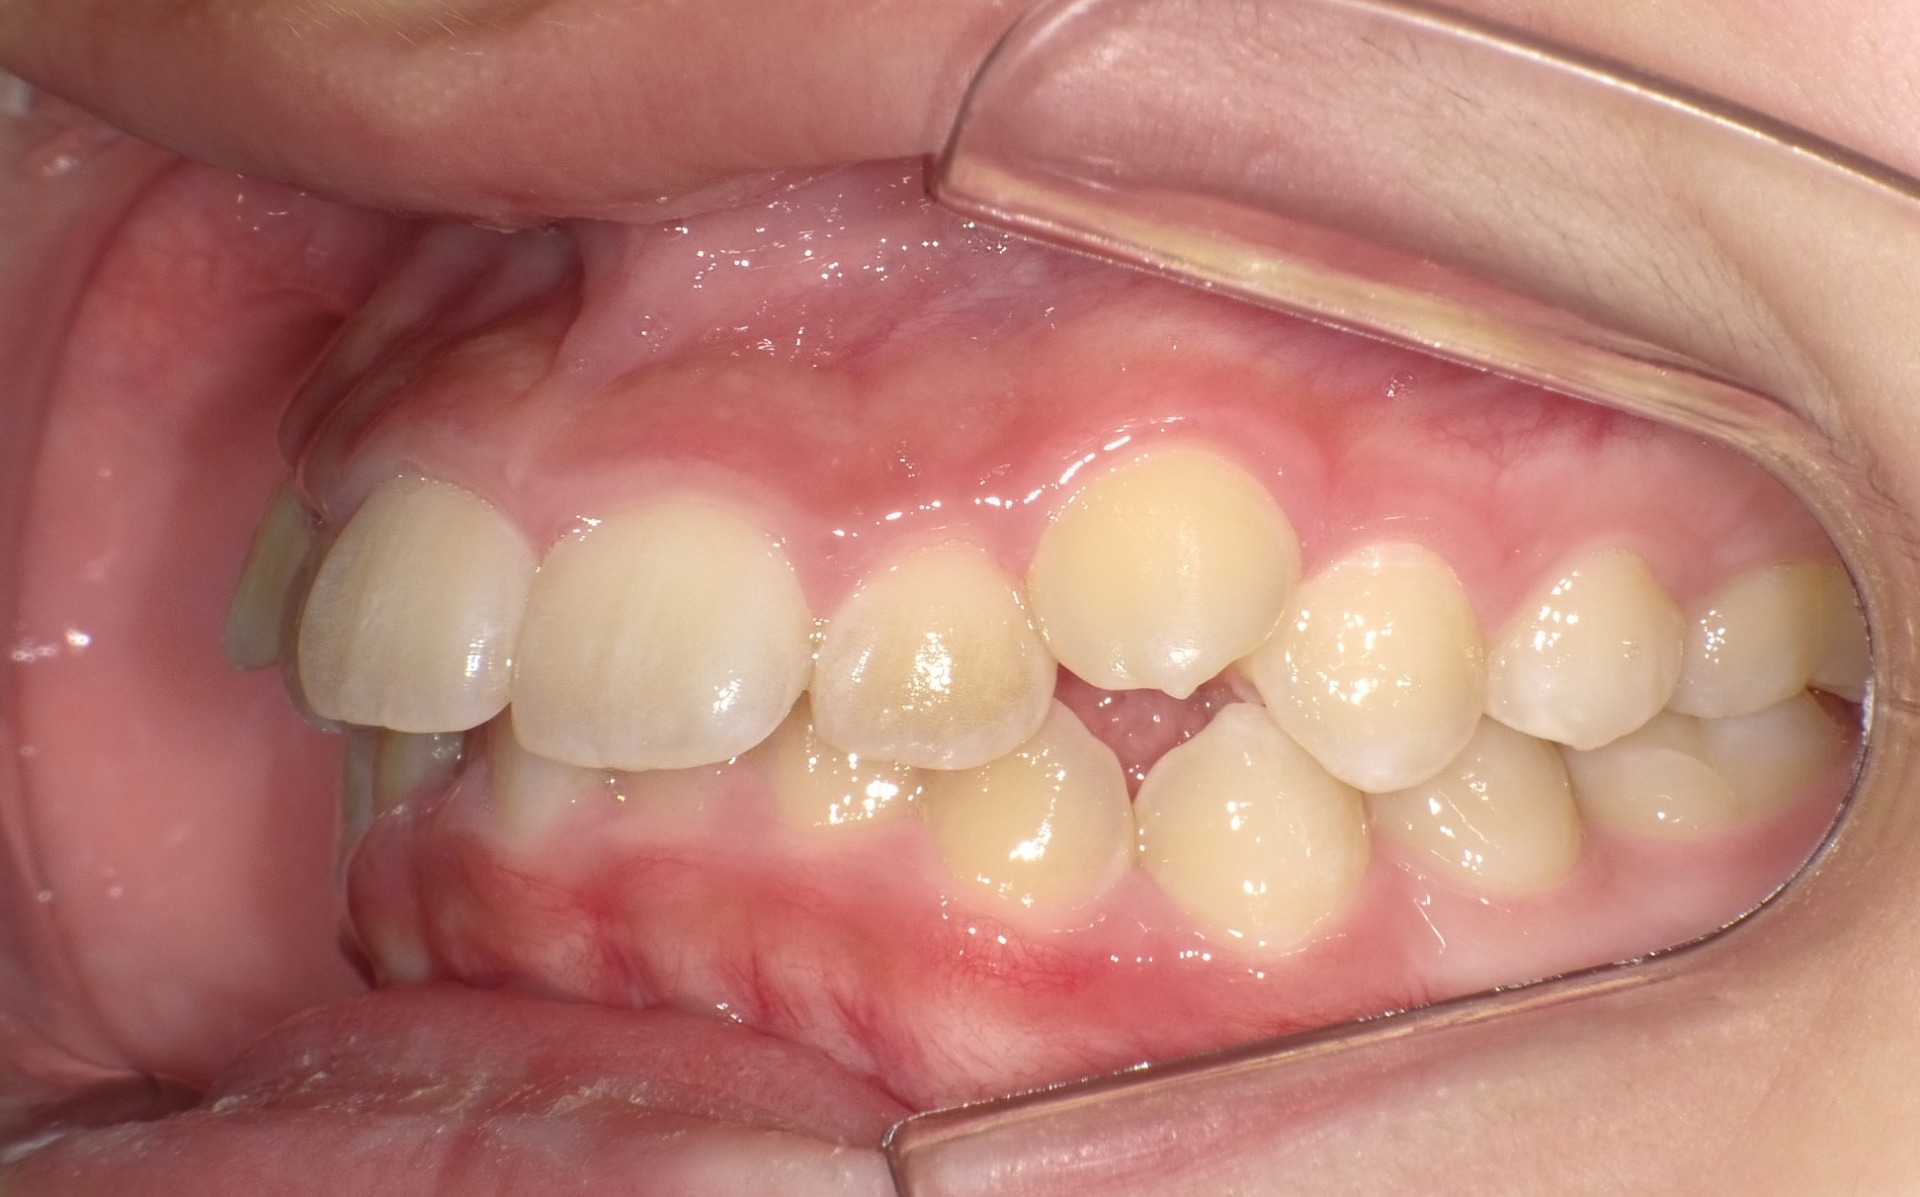

矯正前